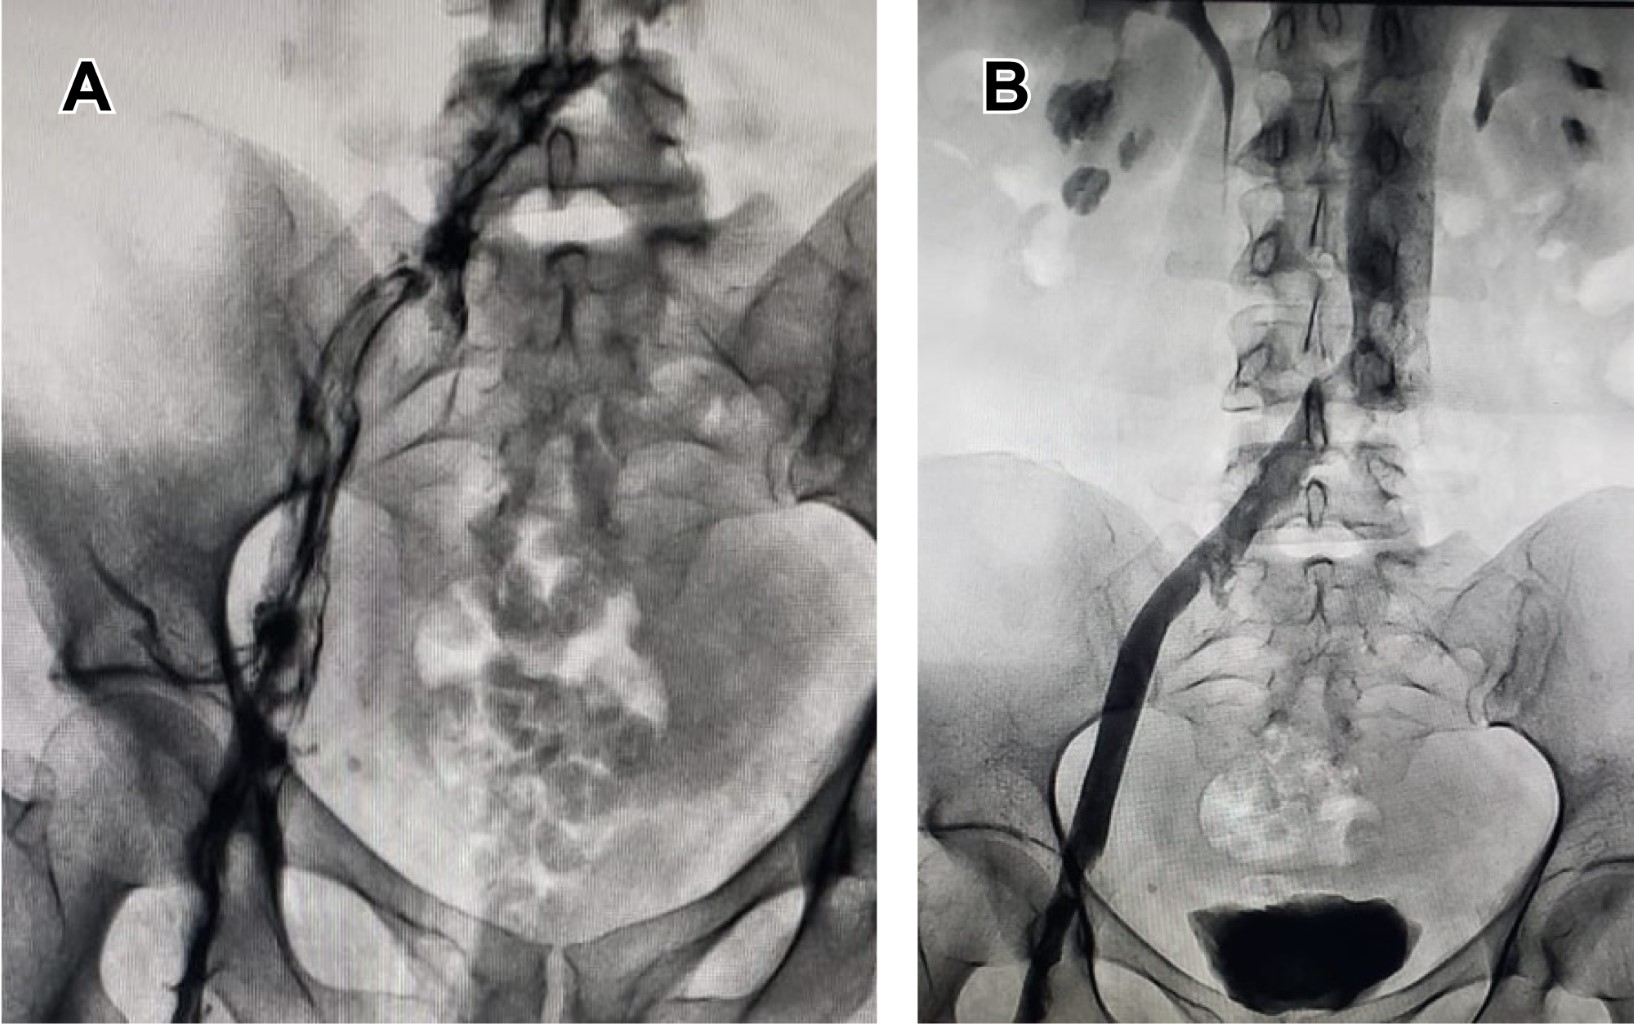

Pharmacomechanical thrombectomy in acute deep vein thrombosis with the Ascher method fast track

The first report of one case of pharmaco-mechanical thrombectomy with the Ascher technique, resolving an acute iliofemoral deep vein thrombosis in a single session was at the Hospital Médica Campestre located in Leon; Mexico.

Figure 1

Figure 2